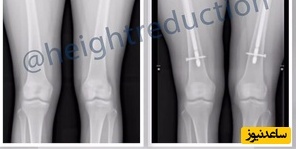

بر اساس توضیحات کلینیکهای ترکیه، معمولاً با کوتاه کردن استخوان ران (فمور) یا ساق پا (تیبیا) انجام میشود. استخوانها با میله یا صفحه فلزی تثبیت میشوند و ترمیم کامل آن ممکن است تا یک سال طول بکشد. عمل حدود 2–3 ساعت است و پس از آن بیمار به چند ماه فیزیوتراپی و استفاده از ویلچر یا واکر نیاز دارد، در حالی که درد شدید بخشی طبیعی از دوران نقاهت است.هزینه این جراحی در ترکیه بین 15 تا 35 هزار دلار گزارش شده و بیشتر متقاضیان از کشورهای غربی هستند.